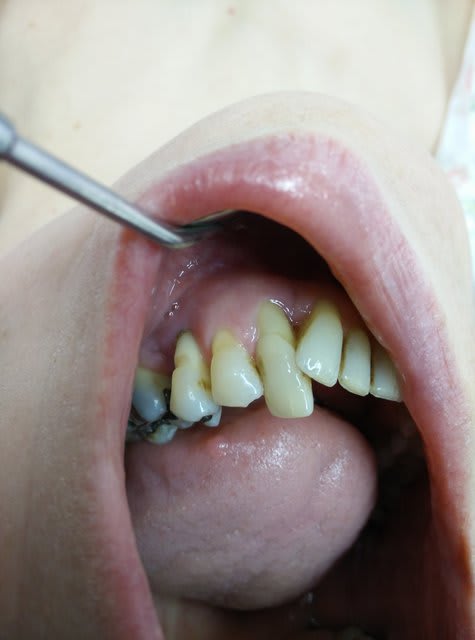

patiente de ce matin, vient car la 35 bouge. gencive dépressive à la palpation en regard de 35, à priori plus du tout de table vestibulaire.

la 33 est très eggressée et prend bcp lors de la cinétique mandibulaire.

La 34 ne bouge pas.

Patiente 62 ans, non fumeuse ras.